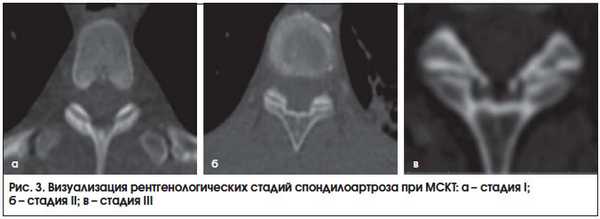

Внедрение в практику МСКТ сделало доступной визуализацию дугоотросчатых суставов, которая была затруднительна при стандартной рентгенографии. Представляем серию томограмм (рис. 2 и 3), демонстрирующих различные стадии спондилоартроза.

Данная патология называется - спондилоартроз. Она является идеальным объектом для МРТ и СКТ исследований. На КТ и МРТ врач-радиолог может увидеть те же признаки, которые видно и на классическом рентгене, но их можно увидеть раньше, четче и точнее определить объем поражения. В каком-то смысле это зависит не только от высокой четкости КТ и МРТ сканов, но и обуславливается тем, что некоторую патологию лучше искать именно в аксиальной плоскости. Какие же проявления может увидеть врач-радиолог? Краевые костные разрастания (остеофиты) на суставных отростках, которые имеют плотную костную структуру и за счет которых определяется увеличение размеров суставных отростков по типу гипертрофии, с сохранением правильного соотношения губчатого и компактного вещества; равномерно или неравномерно сужение суставной щели; иногда определяется субхондрально расположенные кисты или даже газ «вакуум-феномен», также возможно развитие периартикулярных обызвествлений, что в итоге приводит к существенно деформации и увеличения в объеме всего сустава и, как следствие, появляются постоянные жгучие боли в позвоночнике, которые могут отдавать даже в ноги.